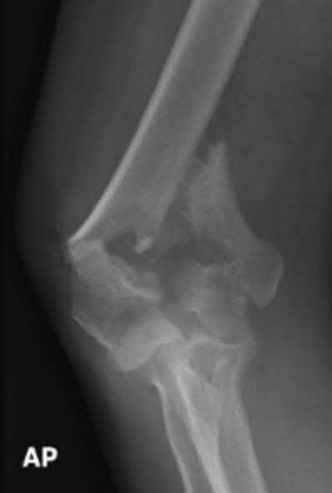

Question 12

A 55-year-old patient presents with a slowly enlarging, painful mass in the proximal humerus.

Biopsy reveals a hyaline cartilage matrix with cellular atypia, confirming a diagnosis of central conventional chondrosarcoma. Which of the following genetic mutations is most frequently identified in this specific tumor?

Explanation

Mutations in the isocitrate dehydrogenase genes, IDH1 and IDH2, are found in up to 50-60% of central conventional chondrosarcomas and enchondromas. EXT1 and EXT2 mutations are characteristic of multiple hereditary exostoses (osteochondromas). GNAS mutations are seen in fibrous dysplasia. TP53 and RB1 mutations are hallmark aberrations in osteosarcoma.